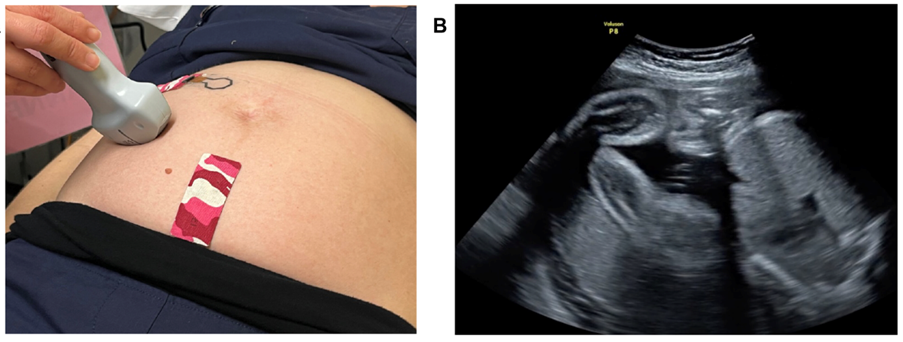

Исследователи из Monash University разработали носимый «Band-Aid-подобный» патч, который позволяет неинвазивно фиксировать движения плода через кожу живота.

- Размер и конструкция: тонкий патч ~10–14 см², состоящий из двух легких датчиков, который крепится на поверхность живота.

- Клиническая проверка: при испытаниях с участием 59 беременных женщин устройство достигло >90 % точности в обнаружении движений плода (кики, повороты, растяжки).